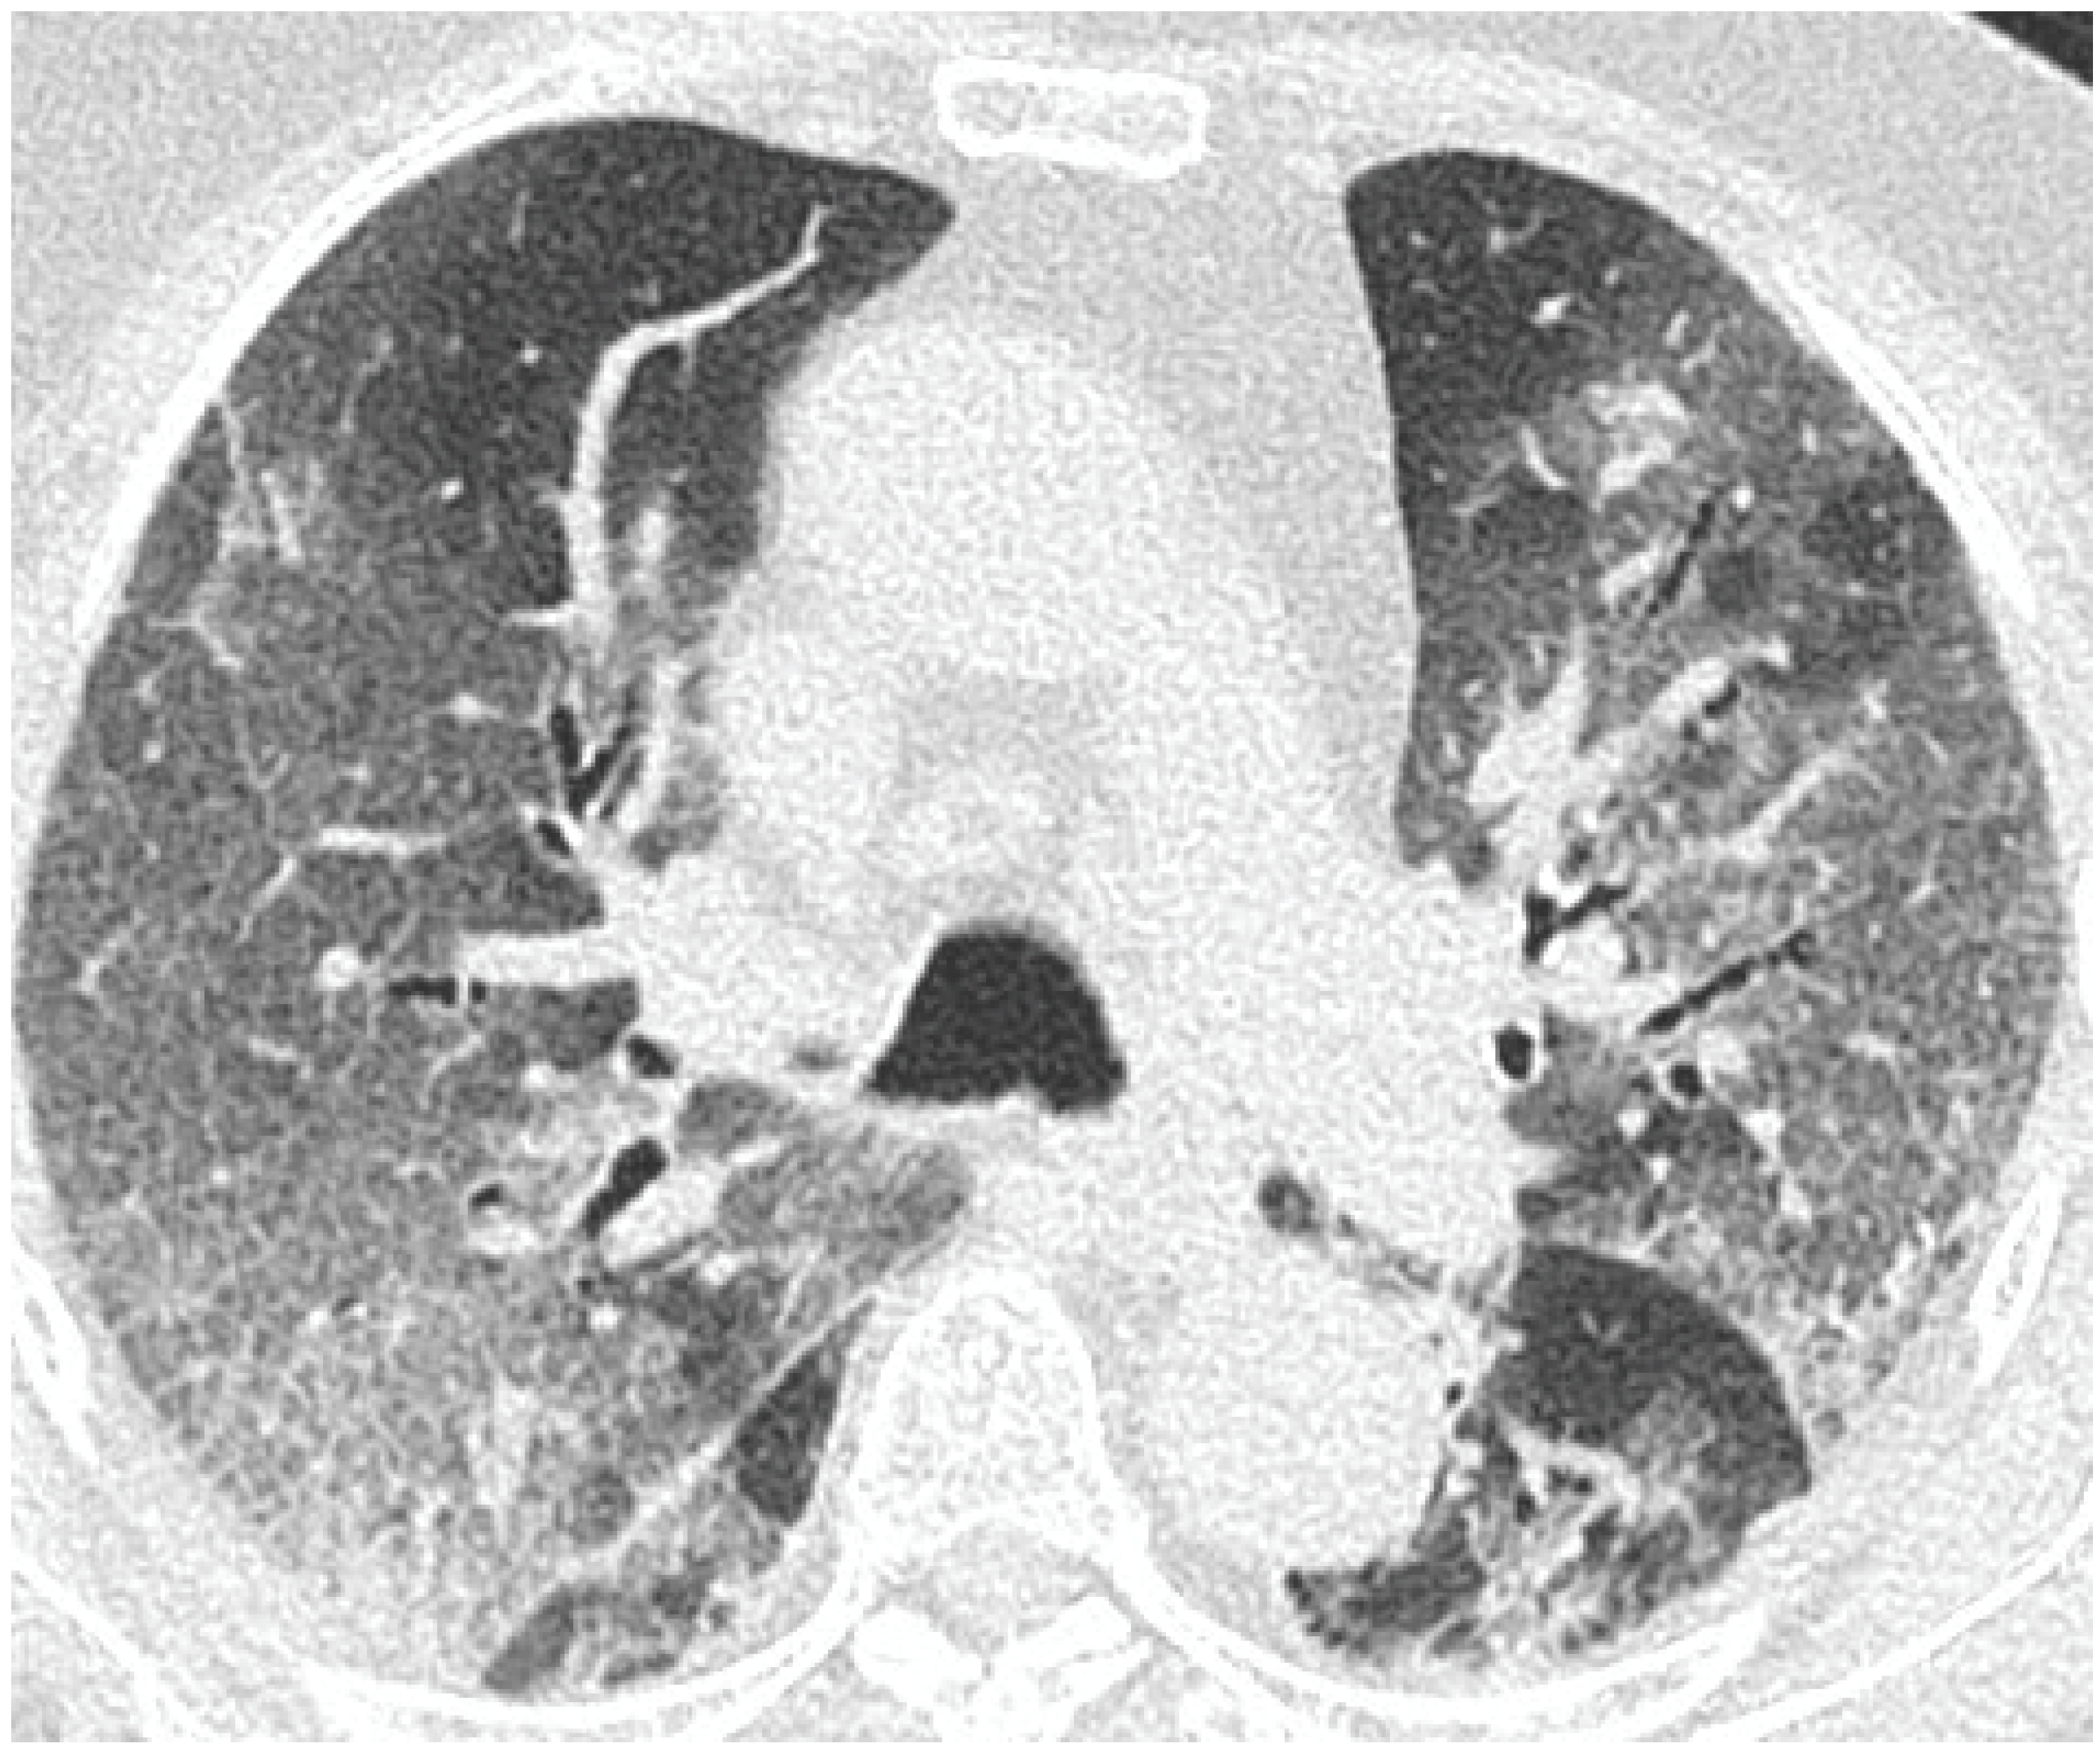

- GGO was defined as hazy increased attenuation of lung with preserved bronchial and vascular margins;

- Consolidation was considered an increase in pulmonary parenchymal attenuation that obscures the airways and vessels;

- Crazy paving was the area of GGO with coexisting thickening of interlobular septae;